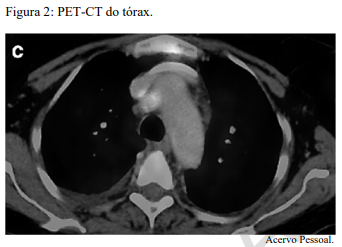

Um paciente de 62 anos de idade, tabagista ativo, cerca de 180 anos-maço, queixa-se de cansaço, tosse seca e perda de peso; por isso, procurou atendimento médico. O paciente referiu que pesava 100 kg e perdeu 10 kg. Realizou-se tomografia computadorizada de tórax, com evidência de lesão sólida de 2,1 cm em topografia de lobo inferior à direita, sólida, espiculada, com margens bem definidas e densidade de partes moles, assim como linfonodomegalia paratraqueal direita de 1,5 cm, paratraqueal esquerda de 1,2 cm e subcarinal de 2 cm. O paciente foi submetido a PET-CT de corpo inteiro, com evidência de hipercaptação de radiofármaco pela lesão (SUV 12) e eplo linfonodo representado na figura 2 a seguir.

Trata-se de um estadiamento clínico T1cN3.